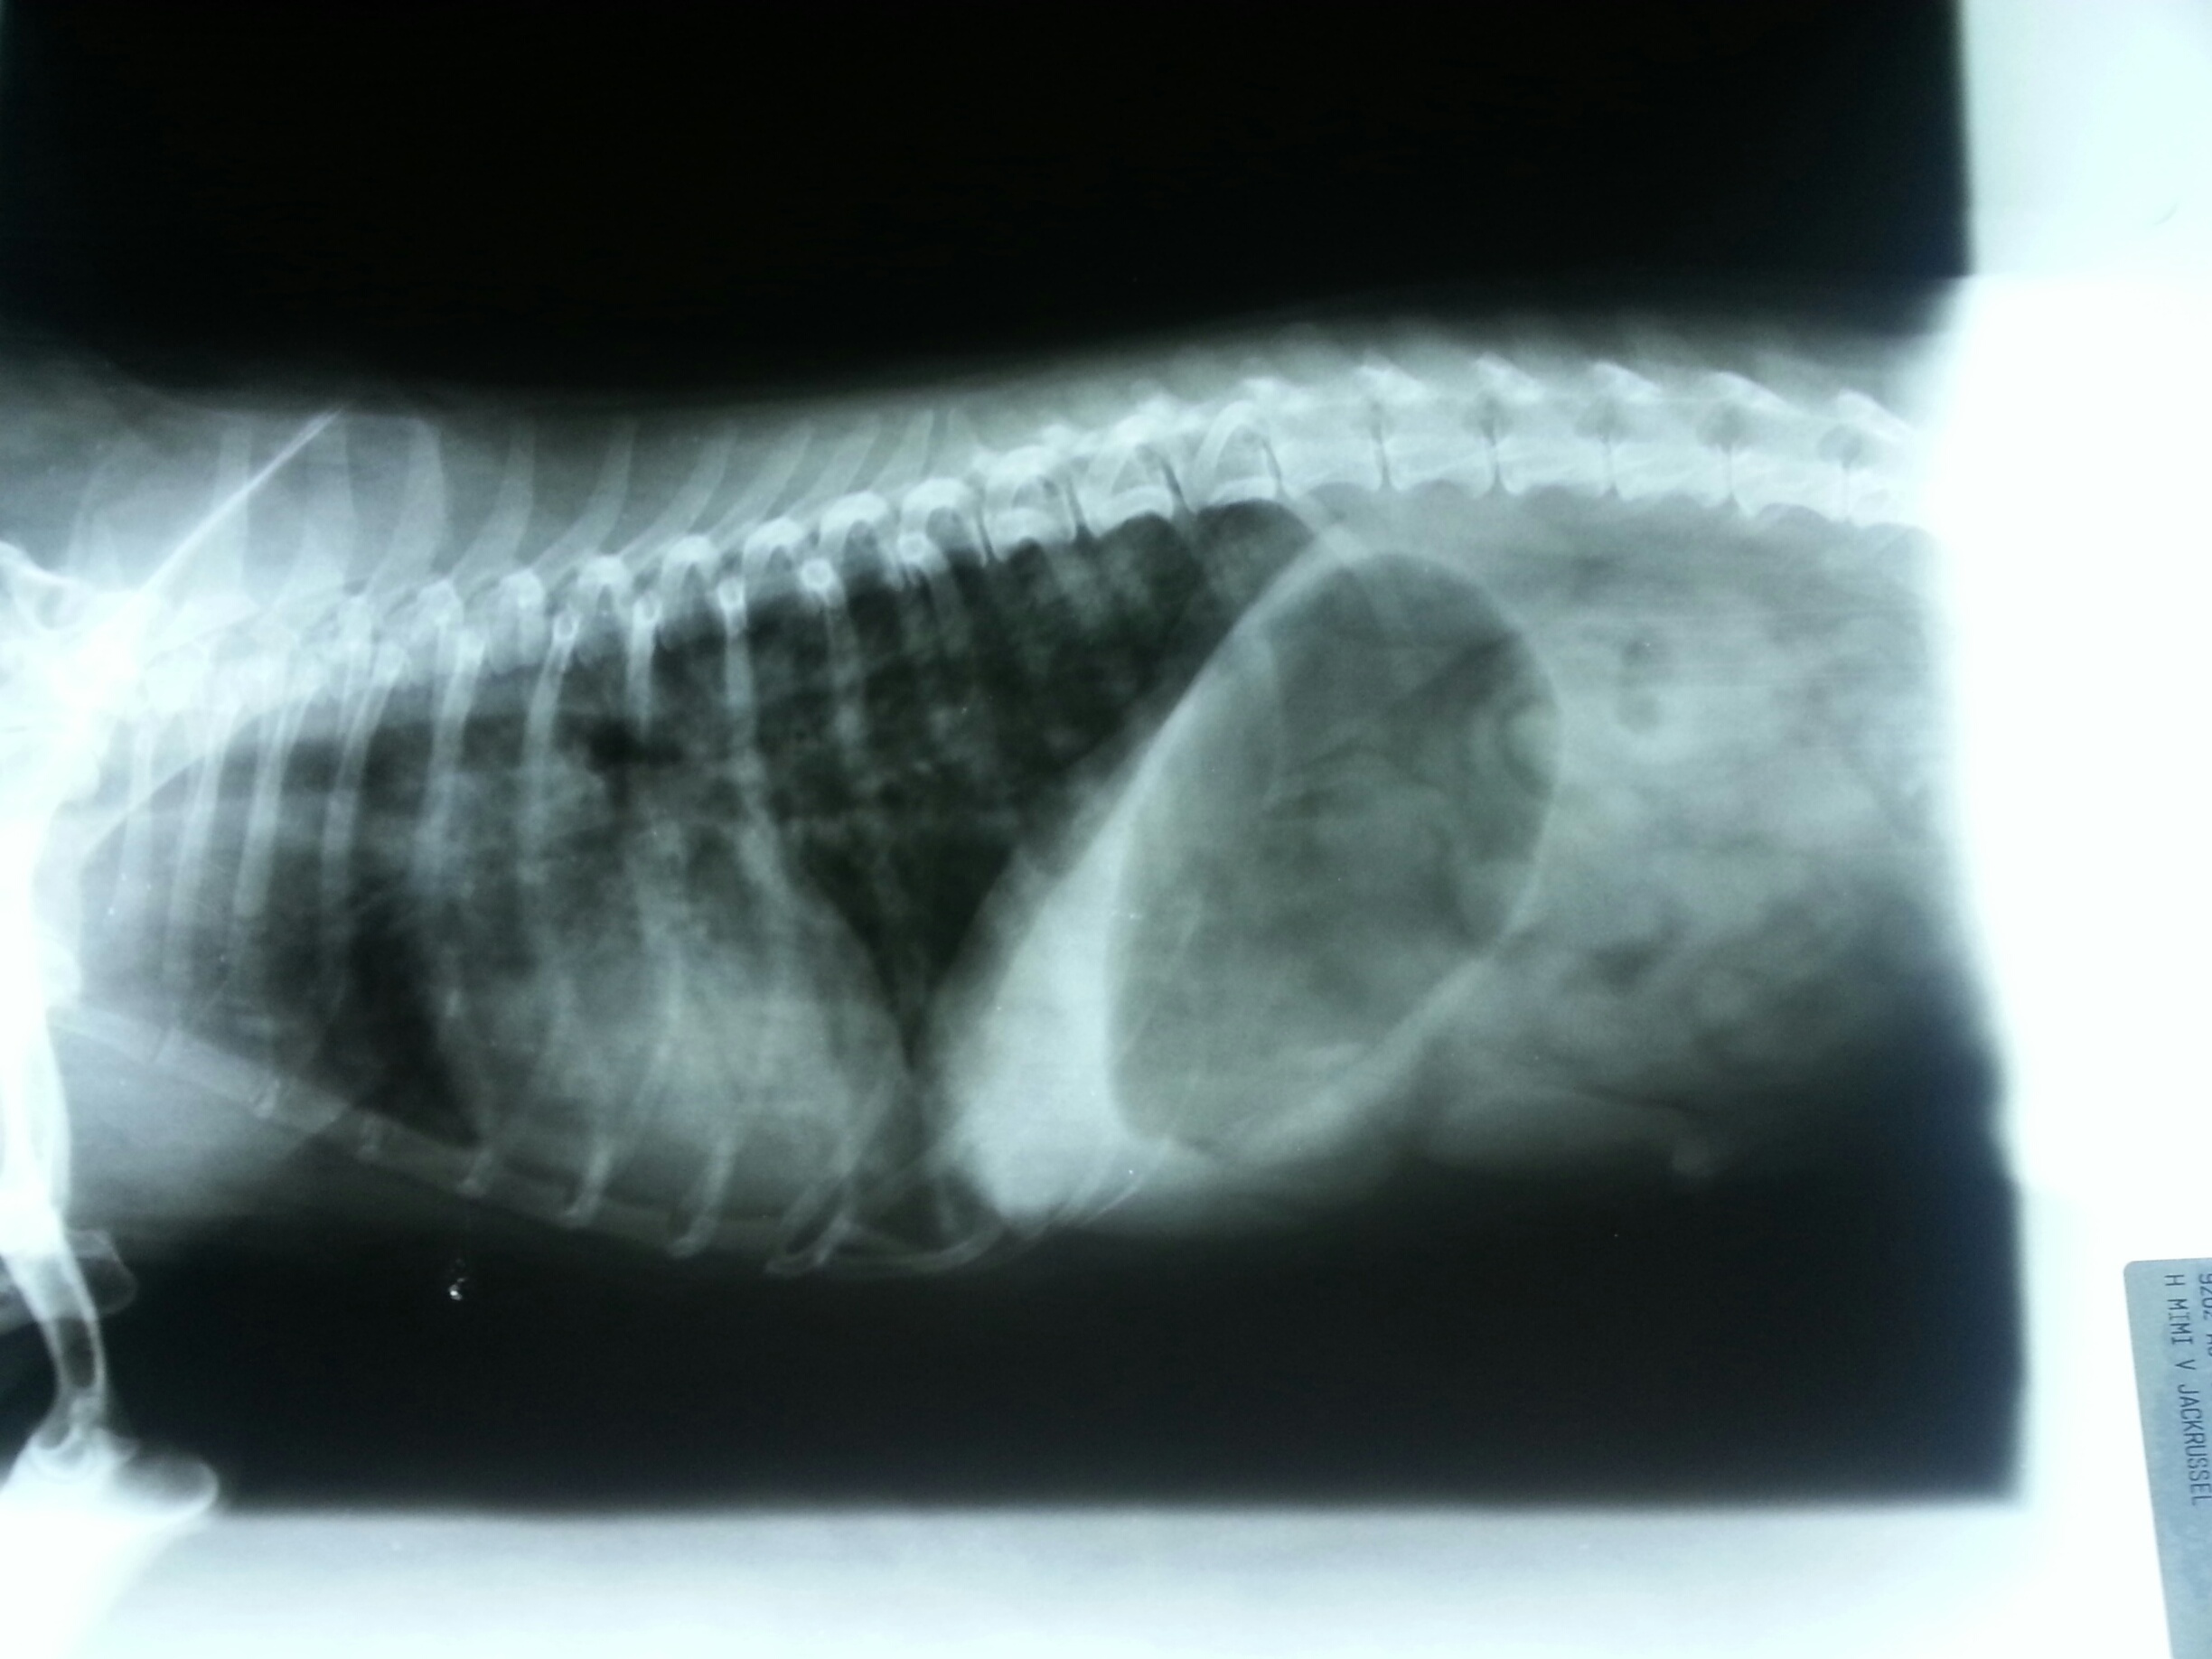

De afbeeldingen verspreid over de hele website zijn allemaal foto’s van eigen huisdieren of gemaakt tijdens het werken met dieren in de afgelopen jaren. Neem de tijd om ze te bekijken en kom er zo achter met hoeveel dieren er al gewerkt is!